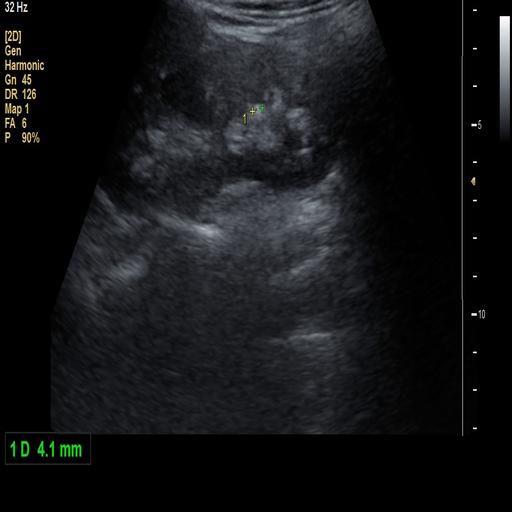

数据样例

结石肾脏样例